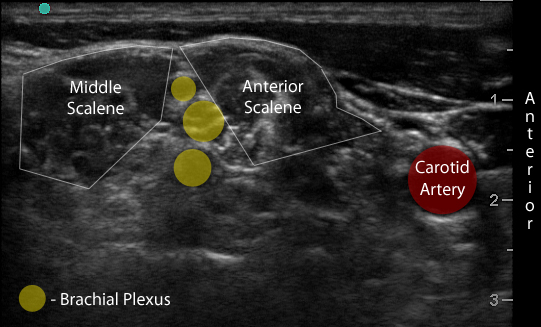

Figure 1. Transverse view over the sternocleidomastoid

Figure 2a. Transverse view through the interscalene space

Figure 2b. With labels

- Use a high-frequency 8-12 MHz linear probe and begin scanning transversely over the anterior neck at the level of the cricoid. (Figure 1)

- Probe indicator oriented to operator’s left.

- Depth should be set between 4-8 cm, depending on the size of the patient’s neck.

- Trachea should be clearly seen as a midline hyperechoic arc.

- Slide the probe laterally to the lateral border of the sternocleidomastoid (SCM) (Figure 1), which is a thin muscle superficial to the carotid and jugular.

- Move the probe inferiorly to identify the anterior scalene muscle deep to the lateral border of the SCM. (Figure 2)

- Triangular muscle that is thicker caudally

- Lateral to the internal jugular vein

- If not apparent, slide the probe in a cranio-caudal direction along the lateral border of the SCM to find it

- Identify the middle scalene muscle posterior to the anterior scalene muscle.

- The interscalene space is between these 2 scalene muscles and contains the brachial plexus

- Visualize the brachial plexus here as a stack of circles with hypoechoic centers

- The plexus will look more echogenic, bundled and honeycombed in the caudal interscalene space